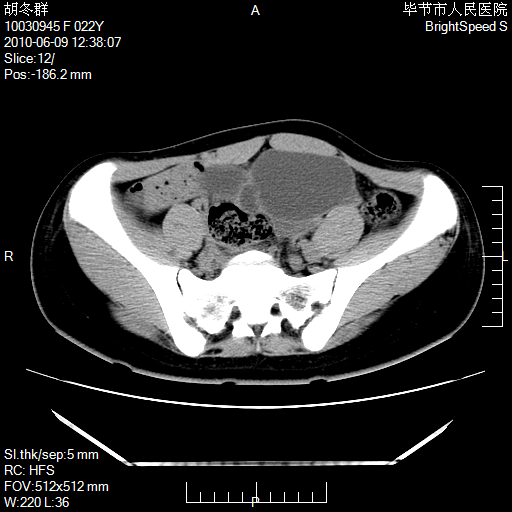

患者23岁,发现腹部包块3月。

左侧卵巢囊腺瘤或囊腺癌

盆腔内囊性占位性病变;考虑左侧卵巢囊腺瘤。

有分隔、壁薄,支持考虑左侧卵巢囊腺瘤。

左侧卵巢浆液性囊腺瘤。

有分隔、壁薄,支持考虑左侧卵巢囊腺瘤。排尿后,膀胱缩小,由于重力作用,肿块下移就到了膀胱位置,很好理解。